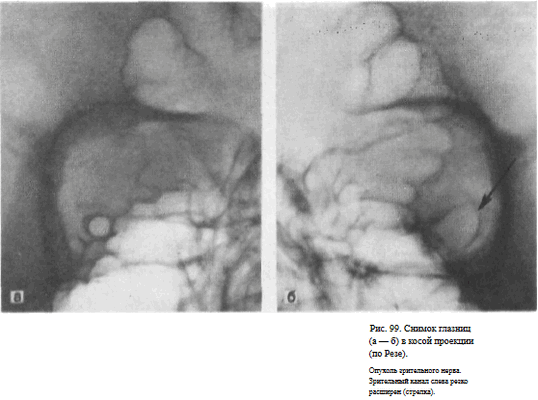

СНИМОК ГЛАЗНИЦЫ В КОСОЙ ПЕРЕДНЕЙ ПРОЕКЦИИ (СНИМОК ЗРИТЕЛЬНОГО КАНАЛА ПО РЕЗЕ)

Назначение снимка. Основное назначение снимка — получение изображения зрительного канала, Как правило, для оценки ширины и формы канала прибегают к последовательной съемке правой и левой глазницы.

Информативность снимка. На снимке отображается зрительный канал, имеющий обычно неправильно-округлую форму с четкими резкими контурами. Видны также вход в глазницу, решетчатые ячейки (рис. 98, а, б). Расширение зрительного канала, возникающее при опухолях зрительного нерва, как правило, может быть достоверно выявлено только путем сравнительного анализа снимков правой и левой глазницы (рис. 99, а, б). Поэтому снимки глазниц в косой проекции по Резе всегда следует производить с обеих сторон.

Критерии правильности технических условий съемки и правильности укладки. На снимке должна быть четко видна структура костей.

Изображение зрительного канала при правильной укладке проецируется вблизи наружной стенки глазницы в виде четкой кольцевидной тени.

Наиболее частые ошибки при выполнении снимка. При неправильном угле наклона головы и неправильной центрации пучка излучения отображение зрительного канала нечеткое. При грубом нарушении правил укладки зрительный канал на снимке неразличим.